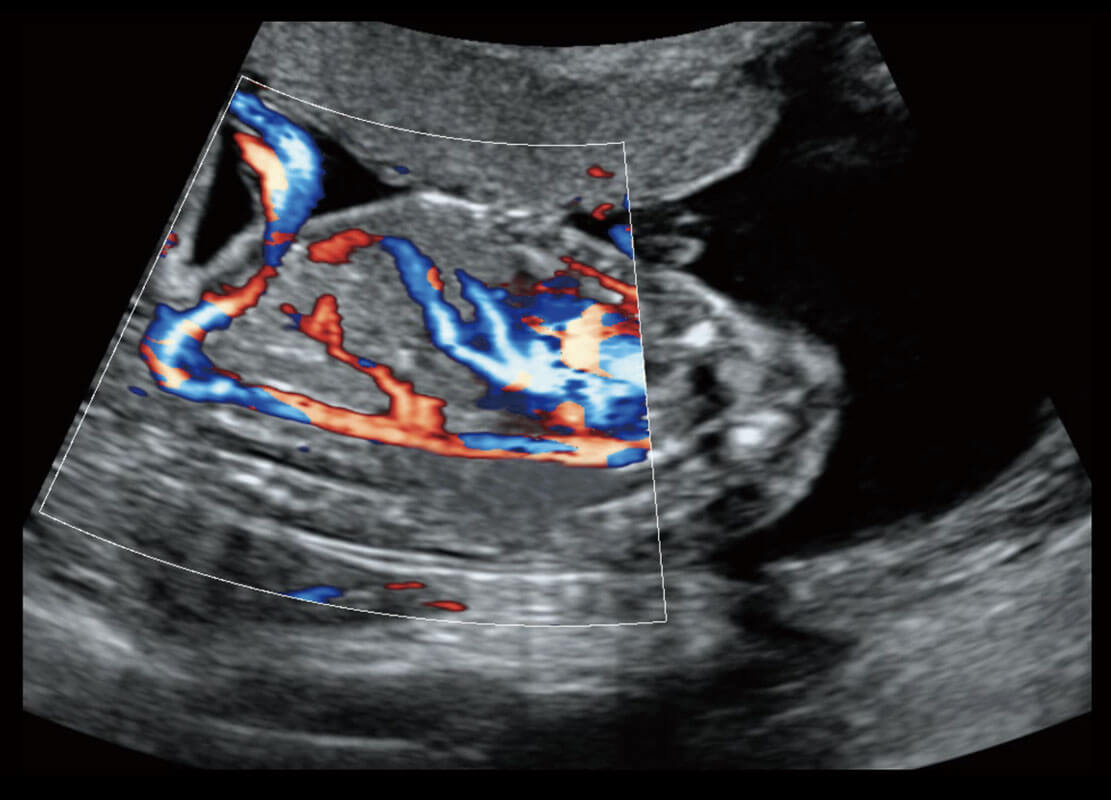

P60搭载一系列胎儿心脏成像技术,实现精细的胎儿心脏评估。

右室双出口